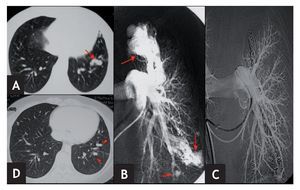

Figura 2 Paciente n.º 3. A) TC torácica donde se observa un grueso vaso pulmonar en língula. B) Angiografía pulmonar izquierda selectiva donde se aprecian varias malformaciones arteriovenosas pulmonares (MAVP) en LSI y língula de tipo complejo (una rama aferente gruesa y múltiples venas eferentes) (flechas). C) Angiografía pulmonar izquierda selectiva postembolización concoilsdonde se observa exclusión completa de todas las MAVP. D) TC torácica de control a los 37 meses postembolización. Obsérvense loscoils (cabezas de flecha) y la ausencia de opacificación de las MAVP.

El seguimiento de los pacientes ha sido clínico en todos los casos y, en 4 de ellos, también radiológico mediante TC de tórax. Todos los pacientes se encuentran asintomáticos tras un período de seguimiento medio de 46 meses (rango, 25-98) y en los 4 en los que se ha realizado control mediante TC de tórax, en ninguno se ha apreciado repermeabilización de la/s MAVP (fig. 2). En el paciente en el que no fue posible embolizar todas sus MAVP, en los sucesivos controles radiológicos las malformaciones han permanecido estables.

De nuestros 4 pacientes a los que se les ha realizado TC de tórax con contraste, en ninguno se ha observado recanalización de la malformación (fig. 2). Las MAVP que no se lograron embolizar en el paciente 3 permanecen sin cambios en la TC de control a los 37 meses. En la bibliografía se han publicado tasas de repermeabilización que oscilan desde el 318 al 131, 153, 1719 o incluso 57 %20. No obstante, es muy posible que nosotros no hayamos detectado ninguna recanalización por tratarse de una serie pequeña, aunque el seguimiento medio ha sido largo (46 meses). No parece haber diferencias en cuanto a la tasa de repermeabilización con relación al material empleado en el tratamiento (coilso balones)1. Entre los mecanismos implicados en la recanalización se han descrito los siguientes: número insuficiente decoils o de tamaño inadecuado19, su colocación muy proximalmente en la arteria de aporte19, presencia de ramas arteriales pulmonares accesorias11, reclutamiento de vasos normales adyacentes a la malformación11 y circulación persistente, en casos de MAVP complejas11. En la mayoría de los casos de repermeabilización de la MAVP es posible llevar a cabo nuevas embolizaciones19.